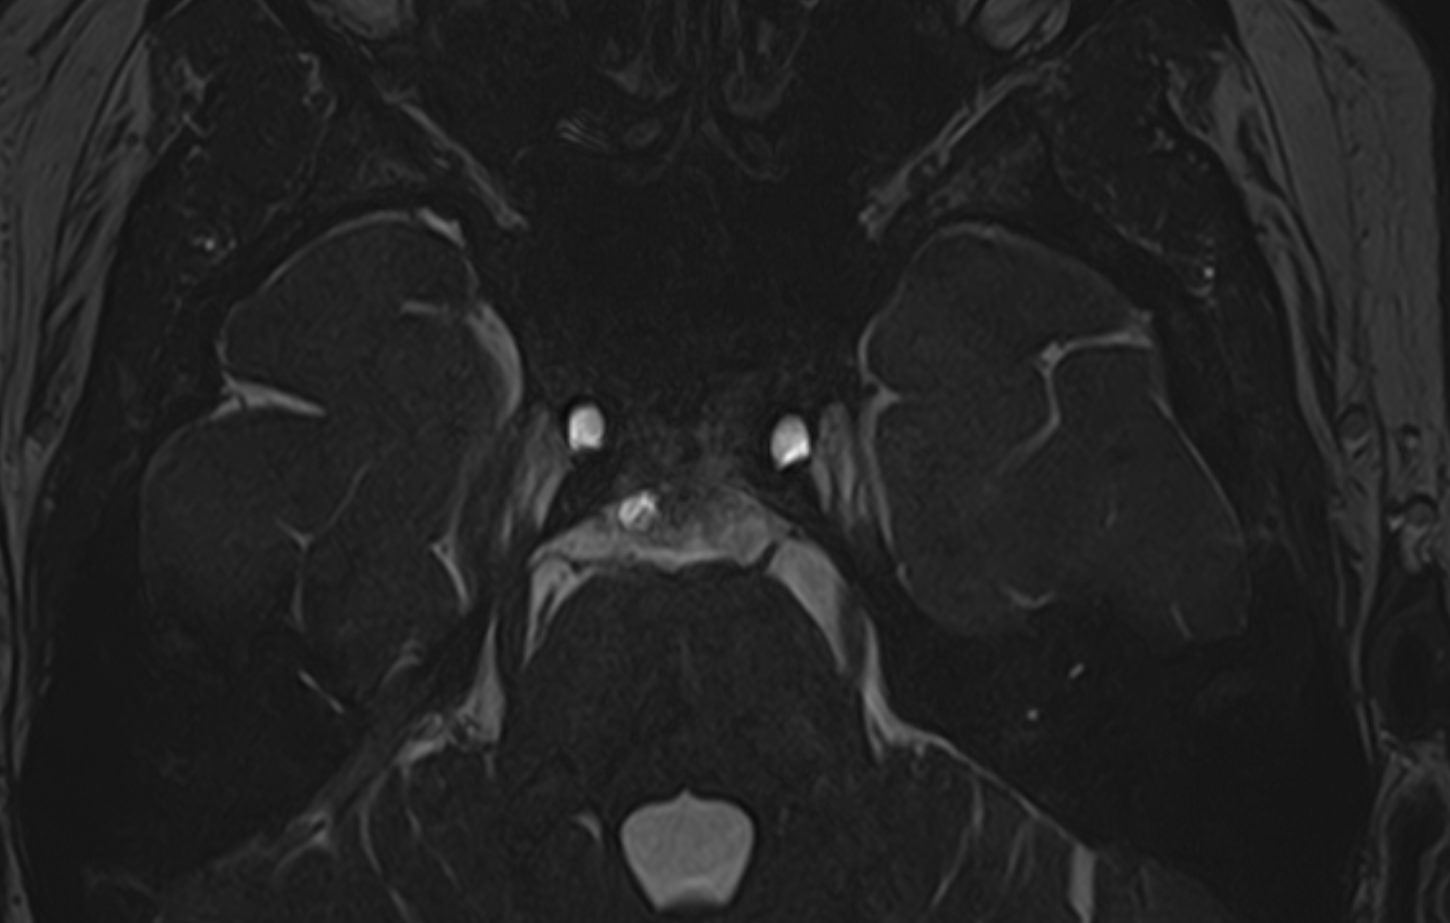

Исследования выполняются на современном высокопольном томографе экспертного класса TOSHIBA VANTAGE TITAN 1,5 Тесла, который использует разные режимы сканирования с толщиной среза от 1мм в различных плоскостях с последующей цифровой обработкой полученных данных для создания трехмерных изображений. МР-ангиография отображает состояние артериальной системы кровоснабжения головного мозга. МР-венография головного мозга позволяет детально изучить особенности венозного русла головного мозга.

Компьютерная программа обрабатывает данные, полученные при сканировании, и формирует объемные изображения как самого мозга, так и сосудистой системы в отдельности без прилегающих тканей. Методики применяются одновременно и взаимодополняют друг друга.

Данное комплексное исследование в большинстве случаев проводится с контрастным усилением, которое необходимо для улучшения визуализации черепно-мозговых нервов. Для этого внутривенно вводится препарат, содержащий гадодиамид (соли металла гадолиния) для получения изображений с высокой четкостью и контрастностью, что способствует ранней диагностике заболеваний головного мозга.